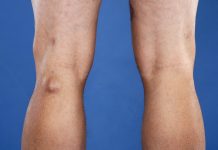

Хруст в суставах — это феномен, который часто ассоциируется с изнашиванием хрящевой ткани, артритом или артрозом. Однако, не всегда причина звука в суставах настолько серьезна. Сам по себе хруст может возникать из-за пузырьков воздуха, образующихся при движении сустава, или из-за трения синовиальной жидкости, смазывающей суставы.

Ключ к лечению патологии заключается в понимании его источника. Если хруст сопровождается болезненными ощущениями, отечностью или ограничением движения, важно обратиться к врачу. Он проведет необходимое обследование и выявит основную причину, на основе чего будет предложен индивидуальный план лечения.